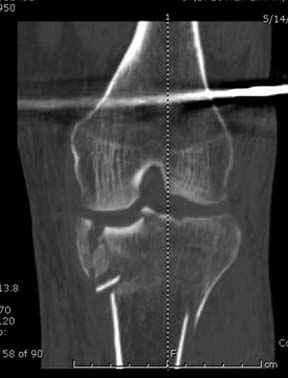

Способ фиксации сам по себе - вполне приемлемый. Однако фиксации должна предшествовать репозиция.

Боюсь, задача восстановления формы суставной поверхности tibia осталась нерешенной.

Имелась центральная компрессия. Проводилась артротомия - суставная линия полностью восстановлена. Произведу контрольные рентгенограммы для доказательства.

Спасибо заранее, с интересом посмотрим. Хорошо бы КТ сделать.

Отдельные переломы тибиал плато и перелом проксимальной трети большеберцовой кости отличаются от переломов тибиал плато с вовлечением диафиза. Здесь перелом тибиал плато типа Schatzker VI, полученный в результате высокоэнергетической травмы. Перелом метафиза образовал отрыв суставной поверхности от диафиза с вовлечением медиального и латерального мыщелков. Двухмыщелковые переломы из-за укрочения опасны развитием компартаментального синдрома, повреждением латерального мениска и связок.

Имеющаяся импрессия не потребовала пластики - достаточным оказалось поднять отломок

Если там действительная импрессия, пустое место без структуральных заполнителей, кость или синтетические материалы, не восстановится, а образуется коллапс, и ось конечности поведет после нагрузки. Кроме того там возможно "болт стяжка"?, в медиальной стороне выступает за кортекс, можно было укоротить! Потом создается впечатление, что не соответствуют мыщелки большеберцовой и бедренной костей? Покажите снимок.

Суббота, суббота! Море, как обманчиво кажется каждым утром выходного дня, свободного времени впереди и можно попытаться объяснить, какой смысл заключается в моём на бегу брошенном мнении, для краткости сформулированном ёмко и однозначно: «говно». Так вот, никакого такого иного, тайного, облегчённого и скрытого смысла в этом жизнеутверждающем и более широком, нежели любой из медицинских терминов слове нет и быть не может. Более того, определённый опыт (если хотите, профессиональная интуиция) подсказывает мне, что если Владимир представит и обязательную вторую, обязательную, и качественную и длинную достаточно рентгенограмму, это не изменит вышеприведённой характеристики. Если не наоборот. Я уже не говорю о КТ. Ибо хорошо упакованные продукты жизнедеятельности ими же и остаются. Качественный состав не меняется. При этом это ни в коей не относится к Вам лично, Владимир. Так я позволил себе охарактеризовать вывешенный Вами результат хирургии в ответ, подчеркну, на Ваш же запрос. Естественно то, к сожалению, подчеркну, естественно, что каждый из нас продуцирует не только блестящие результаты. И чем больше работаешь, тем критичнее к своим случаям стараешься относиться. Ну, хотелось бы, во всяком случае, думать, что это именно так. Но, в нашем случае мы имеем дело не со случайностью и технической помаркой. В данном случае мы имеем дело с ПРОГРАММИРОВАНИЕМ не блестящего результата. И не в комбинации имплантатов дело. Я совершенно не противник комбинирования и сам не часто, но использую это. Приходится, так как и архитектоника перелома иногда заставляет, и экономика может диктовать. Конечно, с моей точки зрения 41С3.3. (или Шацкер 6) не лучшая платформа для такого комбинирования, но, подчеркну, не в этом дело. Или не только в этом. В другом. В Вашей оценке ситуации до операции и в предоперационном планировании, прежде всего. Говорят: „failing to plan means planning to fail“. На русском не так чётко и чуть длиннее, но суть остаётся той же: «Провальный предоперационный план есть не что иное, как планирование хирургического провала». Мне не хочется анализировать каждый из введённых Вами винтов (болтов-стяжек?, что и куда там торчит…), хотя КАЖДЫЙ из этих имплантатов должен нести смысловую нагрузку. Давайте попробуем разобраться, как дОлжно делать, ну а выводы, как всегда, каждый делает сам.

И так, высокоэнергетическая травма – это, прежде всего, тяжёлое повреждение мягких тканей со сломанной костью внутри. Относится ли данное утверждение к переломам плато? И да, и нет. Значительная часть наших пациентов с переломами плато – это люди пожилого и старческого возраста с низкоэнергетической травмой. Как правило, это низкоэнергетические повреждения с отсутствием контузии, фликтен, то есть хорошим состоянием мягких тканей, где в результате перелома нарушена, прежде всего, механическая ось конечности. Мягкие ткани позволяют оперировать нам такие переломы в ранние сроки. Но, главная проблема, с которой мы сталкиваемся здесь – это проблема фиксации порозной кости. Вот здесь и уместны блокируемые имплантаты (благо, в отличие от нашей работы 10-15 лет назад, сейчас и продукта данного, и производителей на рынке предостаточно в разном ценовом диапазоне). Имплантаты прежних генераций здесь используются с трудом, нужно хорошо знать классическую технику, пользоваться пластикой, не забывать о том, что банальный костный цемент может быть реальной «палочкой-выручалочкой». Но, в нашем случае – другая история. Это высокоэнергетическая травма. И здесь как раз сломанная кость внутри повреждённых мягких тканей. Здесь как раз и доступы, и время, подходящее для операции, и технологии – всё сплетается в один клубок, распутать который нам и помогает нормальный предоперационный план. И так, в случае высокоэнергетического перелома тибиального плато мы сталкиваемся с тяжёлым повреждением мягких тканей, контузиями, фликтенами, риском развития компартмент-синдрома, зачастую переломы носят открытый характер и в своих крайних составляющих сопровождаются повреждением и сосудов, и нервов. Поэтому вначале мы лечим мягкие ткани – то бишь создаём комфортные условия для них. Это может быть шинирующий наружный фиксатор, это может быть и более многими любимый аппарат Илизарова. Условие одно – избегать гипердистракции, это плохо для мягких тканей и даже может способствовать развитию компартмент-синдрома. Мягким тканям должно быть «уютно» в этот непростой для всей конечности период и беспокоить их лишний раз в это тяжёлое время не нужно. Иногда – а это зависит от структуры перелома, стабильности отломков и тяжести повреждения мягких тканей даже хорошо смягчённая, в положении лёгкого сгибания в коленном суставе, очень свободная внешняя повязка сгодится – полимерная или даже гипсовая. Иногда – только дисциплинирующее лёгкое скелетное вытяжение. Главное, если нет компартмента – не трогай! Ждём. И стараемся оперировать в оптимальные сроки, диапазон которых здесь достаточно широк – от 5-6 до 21-23 дней с момента травмы. Морщинки на коже лучше всего подскажут нам это время. Однако, время впустую не теряем – мы обследуем больного и, не побоюсь этого слова, думаем даже, и обсуждаем с нашей бригадой пре-план. Что нам нужно из обследования? КТ – идеально. Однако, что скрывается за утверждением: «КТ – золотой стандарт в обследовании всех пациентов с внутрисуставными переломами»? Ведь то, что перелом, в основном, виден и на банальной рентгенограмме – аксиома. Так вот КТ нам нужна, прежде всего, для адекватного пре-планирования. Для того, что бы решить, какой доступ использовать, что и как репонировать, где и какой имплантат разместить. Срезы – фронтальные, сагиттальные, но, прежде всего, поперечные срезы плато важны. Я приложил файл с фрагментом моей лекции “Approaches to the Proximal Tibia”, что я делал для мастер-курса в Давосе в том году. Прошу прощения за самоцитирование, но что-то уникальное сейчас не представляется возможным подготовить. Так вот, там, где-то ближе к началу, слайд с подробным объяснением того, что мы ищем и как мы можем использовать поперечный срез. Какой фрагмент остался интактным и стабильным, то есть к чему мы всё будем привязывать, где импрегнированная часть кости и нужна ли будет пластика, где идут линии перелома и как нам правильно рассчитать доступ (ы), что бы они прошли как раз над линией перелома аккурат для «открытия данной книги». Ведь одних только доступов для тибиального плато не менее десятка и значительную часть из них, за исключением разве что артроскопического в той или иной комбинации можно использовать в данном случае. Такое планирование делает возможным миниинвазивную хирургию даже при суставных переломах. Естественно, если понимать под миниинвазивностью не только и не столько размер мягкотканого окна, а тот дополнительный вред, который наши манипуляции даже через маленький разрез могут нанести мягким тканям и кости. Именно такое изучение КТ даёт нам представление и о том, - сколько, каких имплантатов и как использовать при каждом конкретном переломе. Нет КТ? Дело хуже. Но трагедии так же нет, ведь и там где она есть, что-то непрерывно ломается, дозаказывается, ожидается и так далее. В этом случае выручают косые рентгенограммы. Под какими углами и сколько – вам решать. Финально, изучая все классические и косые срезы, мы должны сформировать ясную мысленную 3Д картину перелома. Это и поможет нам в выборе имплантатов и их расположения, в том, нужна ли будет пластика, или нет. Конечно, Вы, Владимир, правы, в последнее время наблюдается определённая тенденция менее частого, что ли, использования пластики при внутрисуставных переломах. Связано это с массовым применением пластин новых образцов от разных производителей, но с одной идеологией. Практически полностью отказались от использования пластики при переломах проксимального плеча и дистального луча. Многие не делают этого при переломах пятки (я - делаю). Но вот при импрессии части плато… Ведь пластика – это не заполнение «дырки», это профилактика вторичного смещения столь нагружаемого участка сустава. Если вы можете применить «рафтинг» тонкими блокированными винтами, это ещё может быть оправданным, хотя, повторюсь, я не рискую. Но без него???

Я думаю, что если с новыми, услышанными, например, от экспертов форума, оценками и размышлениями Вы вернётесь к изучению представленной Вами рентгенограммы, то увидите, что вы не восстановили ни плато, ни правильные осевые взаимоотношения. Вы оперировали на отёке, не в оптимальное время. Используя болты-стяжки, вы устроили то, что зачастую называют «костный сэндвич», такое сдавление кости много-много хуже для биологии, чем аккуратно введённая малоинвазивная вторая небольшая пластина с медиальной стороны. К тому же, и это чрезвычайно важно – ни пластина, ни заглублённый гвоздь не предотвращают здесь возможности развития вторичного варусного коллапса плато. А в условиях недостаточности опоры для медиальной суставной поверхности и латерально – ввиду отказа от пластики и отсутствия «рафтинга», слишком уж много «критических точек» нужно пройти данному пациенту. Я не знаю, куда это смотрят концы болтов стяжек? Или это гайки лежат внутрикостно? И прочая, прочая, прочая, что уже, впрочем, отмечено экспертами форума.

Согласен с постами докторов Кульджанова и Волны. В данном случае мы не отмечаем признаков тщательного предоперационного планирования, что сказалось на характере принятого решения и его результате. В нашей клинике, мы бы использовали длинную блокированную пластину по латеральной поверхности, через проксимальное окно отрепонировали бы суставную поверхность, через дистальное фиксация 3-4 винтами в с/3 б/берцовой кости. По медиальной поверхности в качестве поддержки - 1/3 трубчастая или реконструктивная пластина. С большой долей вероятности использовали бы костную аутопластику.